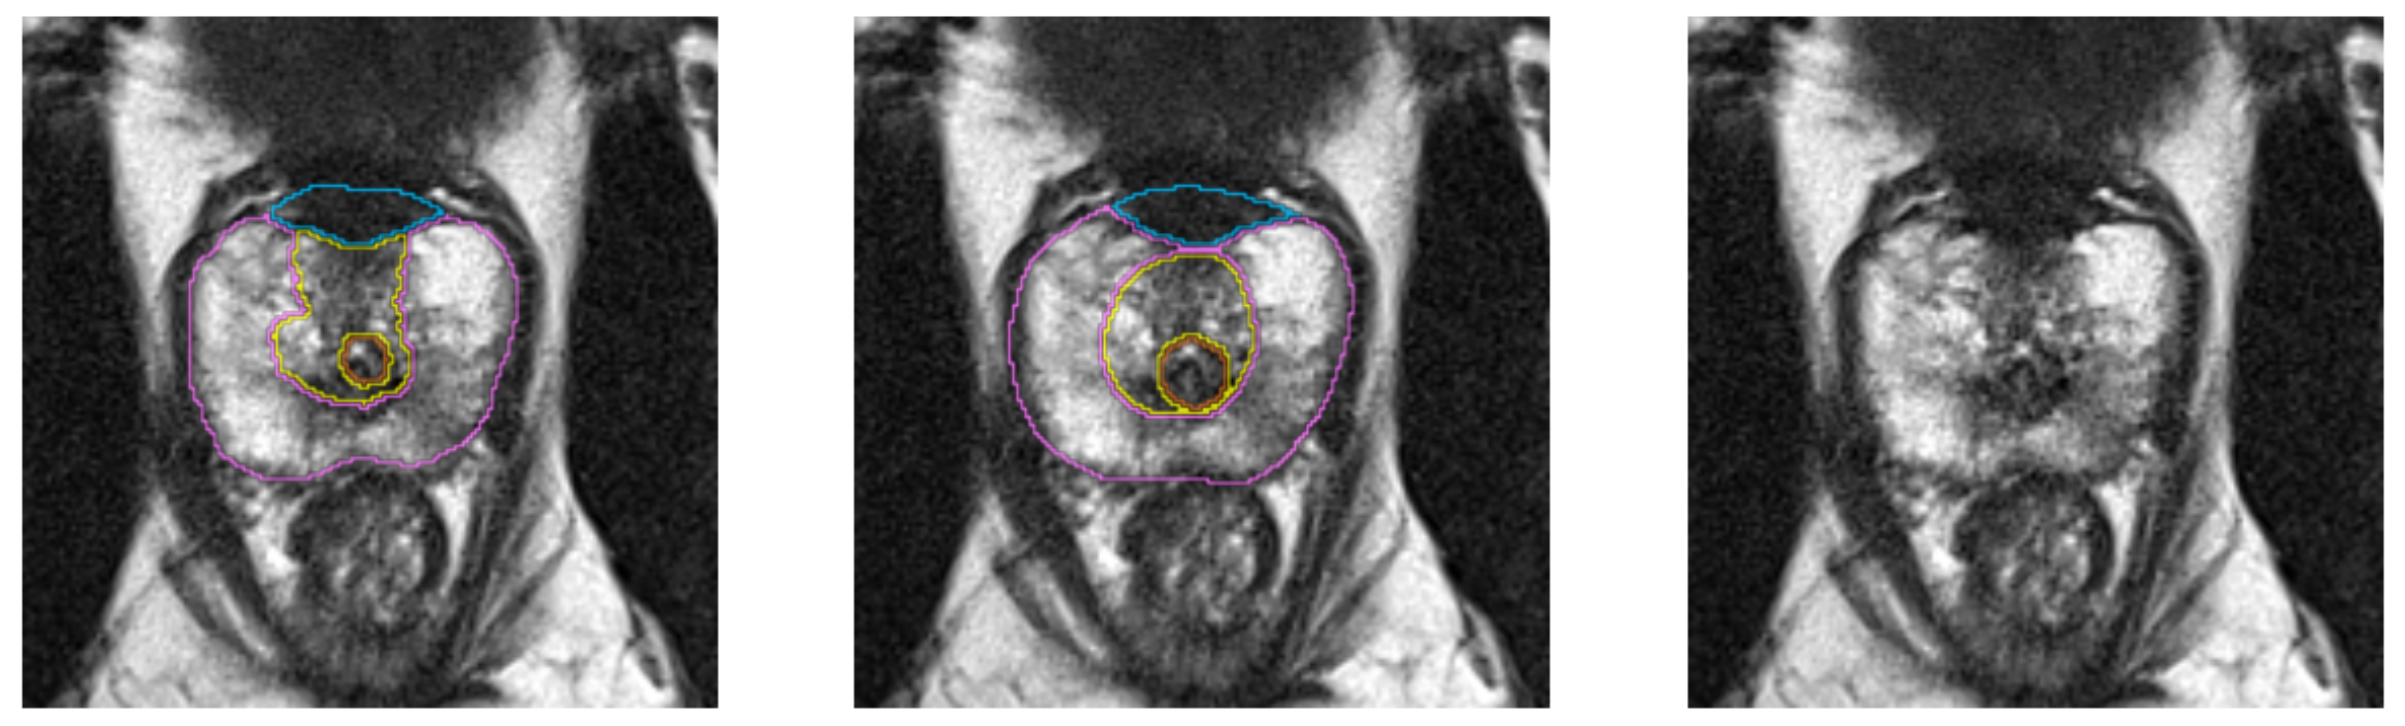

Multi-Label segmentation of anatomic prostate zones in MRI

The goal of this project is to evaluate and extend variants of a volumetric CNN for multi-label segmentation of prostate zones in MR images. The prostate zones are essential for lesion classification and therapy planning. After successful segmentation, a sector map could be extracted that is used for PI-RADS reporting. This has the potential to automate and better standardize prostate lesion location reporting. This project is a continuation of the project that we started in last Winter Project Week. We already have results, but especially in one zone, the algorithm does not work very well and is not stable.

Illustrations